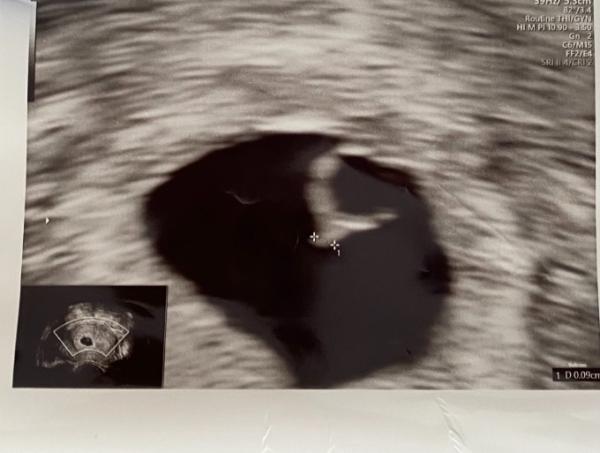

Hey, ich bin ganz verzweifelt und hab mal eine Frage die ihr mir vielleicht beantworten könnt. War heute beim Frauenarzt um die SSW festzustellen. Wäre eigentlich genau bei 6+0 heute. Der FA konnte nur ein 0,09 großen Embryo ohne Herzschlag feststellen und meinte, dass es viel zu klein sei für die Woche. Er hat mir Blut abgenommen und meinte ich solle mich darauf einstellen, dass es in den nächsten Tagen abgeht. Aber ich habe jetzt direkt danach einen Schwangerschaftstest gemacht den von Clearblue, der zeigte 3+ an. Das heißt doch eigentlich, dass das HCG in Ordnung ist oder ? Bin total verwirrt

Ja Gott sei Dank ist der kleine genau 1cm gewachsen und hat einen kräftigen Herzschlag :)